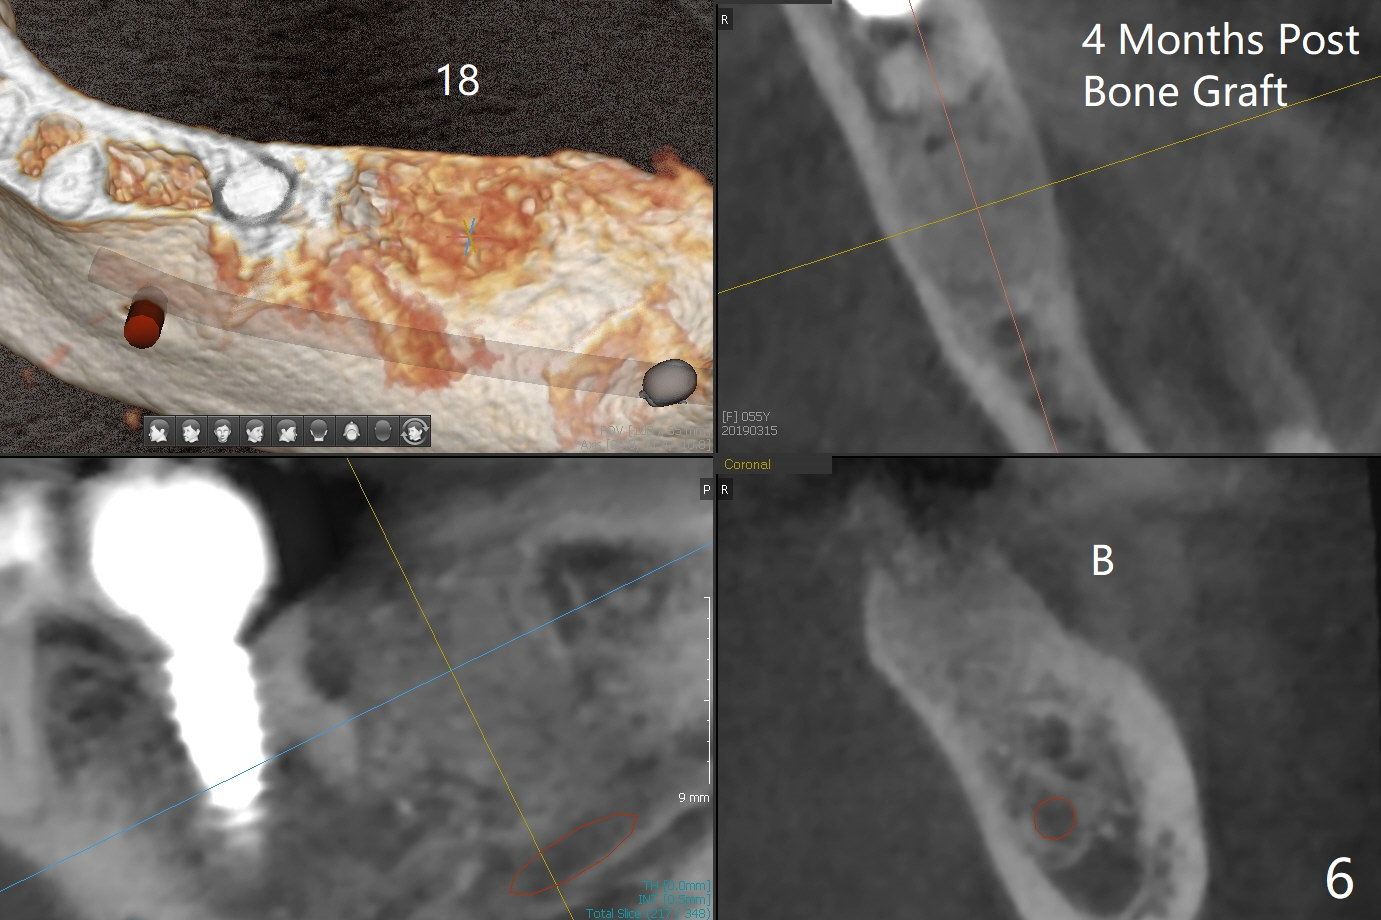

Bone Density Post Extraction with or without Bone Graft

16 Months Post Graft